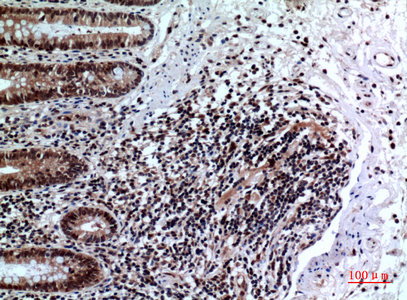

IHC 1/50-1/100 Human,Mouse,Rat

FOXP3 (Forkhead Box P3) is a transcription factor predominantly expressed in regulatory T cells (Tregs), where it plays a critical role in their development, function, and immunosuppressive activity. As a master regulator of Treg biology, FOXP3 ensures immune homeostasis by suppressing excessive immune responses and preventing autoimmunity. Mutations in the FOXP3 gene are linked to immune dysregulation, polyendocrinopathy, enteropathy, X-linked (IPEX) syndrome, a severe autoimmune disorder.

FOXP3 antibodies are essential tools for identifying and characterizing Tregs in research and clinical settings. These antibodies target specific epitopes of the FOXP3 protein, enabling its detection via techniques like flow cytometry, immunohistochemistry, and Western blotting. Due to FOXP3's intracellular localization, staining typically requires cell fixation and permeabilization. Researchers rely on FOXP3 antibodies to study Treg dynamics in diseases such as cancer, autoimmune disorders, and transplant rejection, where Treg populations often correlate with disease progression or therapeutic outcomes. Commercial FOXP3 antibodies (e.g., clones 236A/E7) are validated for human, mouse, and other model organisms, though species cross-reactivity must be confirmed. Recent efforts focus on standardizing FOXP3 antibody specificity to address variability in staining patterns across studies. As Treg-targeted therapies advance, FOXP3 antibodies remain pivotal for both mechanistic research and biomarker development.